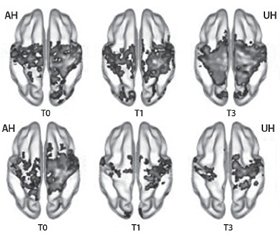

Пластичность сенсомоторных путей оценивалась с помощью функциональной МРТ (фМРТ) исходно, сразу после завершения терапии, а также через три месяца после развития инсульта. При проведении анализа в подгруппе пациентов с нарушением двигательной функции тяжелой степени (FMA < 50, тест Фугл — Мейера) в точке Т0 были проанализированы данные фМРТ 29 пациентов (Церебролизин n = 13, плацебо n = 16). Динамика в сенсомоторной сети продемонстрировала повышение симметричной функциональной связи между билатеральными первичными сенсомоторными зонами коры головного мозга (SM1), которое было значительно более выраженным в группе препарата Церебролизин.

Стоит отметить, что именно в подгруппе с тяжелым двигательным нарушением была выявлена статистическая разница в восстановлении моторной функции, которая оценивалась по тесту Фугл — Мейера (FMA), в пользу группы, получавшей комбинированную терапию (Церебролизин + реабилитационные мероприятия), в сравнении с группой, которая получала плацебо + реабилитационные мероприятия.

Таким образом, данные нейровизуализации подтверждают положительный эффект комбинированной терапии — ранней реабилитации и Церебролизина на активацию процессов пластичности моторной сети. При этом добавление Церебролизина в комплексную терапию способствует более раннему и полному раскрытию реабилитационного потенциала пациента.